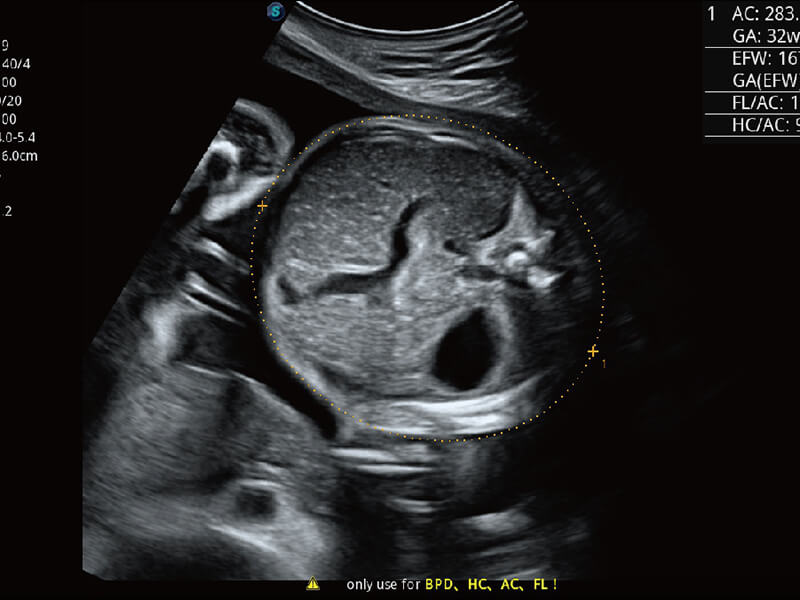

S60探头工艺,从前端信号处理每一个环节采集无损声学数据,真实还原组织原貌,再现解剖细节。

超宽频带技术,为容积成像带来优质的二维图像基础,为您呈现丰富的结构细节,栩栩如生地展示宝宝的宫内形态以及各种组织的立体结构。